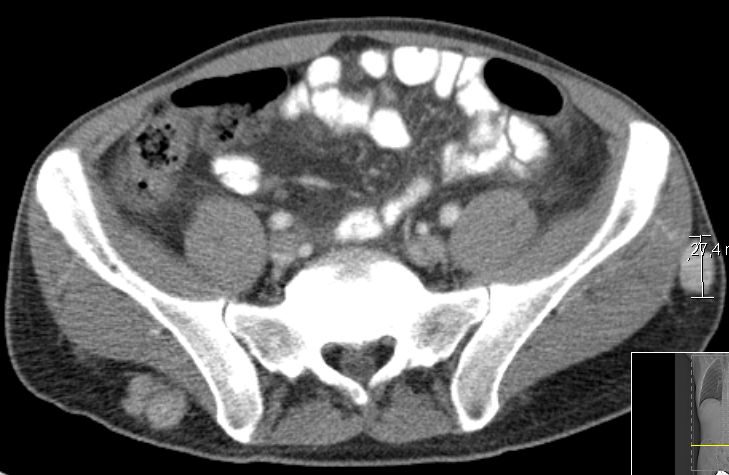

61-jähriger Mann mit einem Nierenzellkarzinom

links mit Lungenmetastasen vor 7 Jahren. Therapie mit Sunitinib, dann Pazotinib,

dann Axitinib, dann Sorafenib. Jetzt Metastase in der kontralateralen Niere.